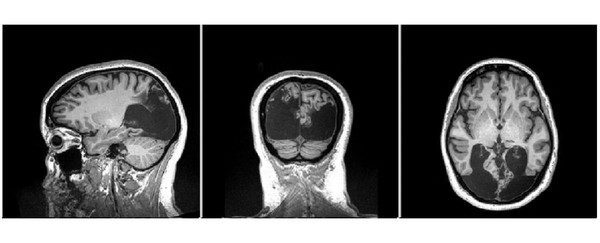

这是由脑部枕叶病变所引起的,而枕叶正是大脑处理视觉的区块。而他们也发现,这可能是Milina的大脑在创伤后展开自救,重新调整了视觉处理系统,保留了剩下的视力可能性。